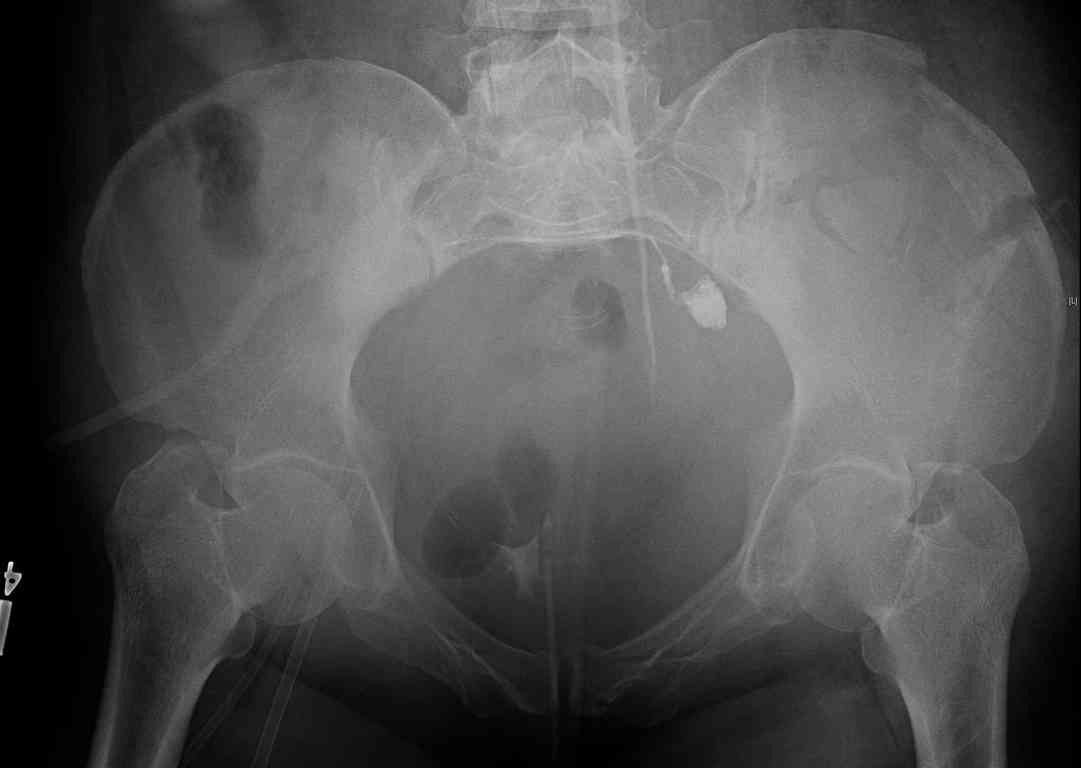

[Ortho] comminuted crescent fx

Any advice would be appreciated:

40 ish female ejected from car. Unstable, DPL negative, went to angio and had her pelvic bleeds embolized after many units of blood. GCS 6, floating elbow, clavicle, bothbones, etc.

My standard approach to  this pelvis would be posterior, reduce/lag/plate  thecrest, reduce/plate the caudal extent on the posterior crest and 1-2 lags back to front. In this case, the crest comminution seems to make plating all

the way to the ASIS useless, as the plate would be on free floating fragments. Would plating the posterior extent of the fracture to secure the

reduction at the SI joint and 2 screws back to front be sufficient fixation? Would anyone do a perc reduction and perc back to front screws, and would that be sufficient if the SI joint could be reduced (although I don't see how this could be accurately reduced closed). Would an ilioninguinal with a pelvic brim plate and posterior column screws be a better approach, although reducing the SI would be more indirect and less accurate?